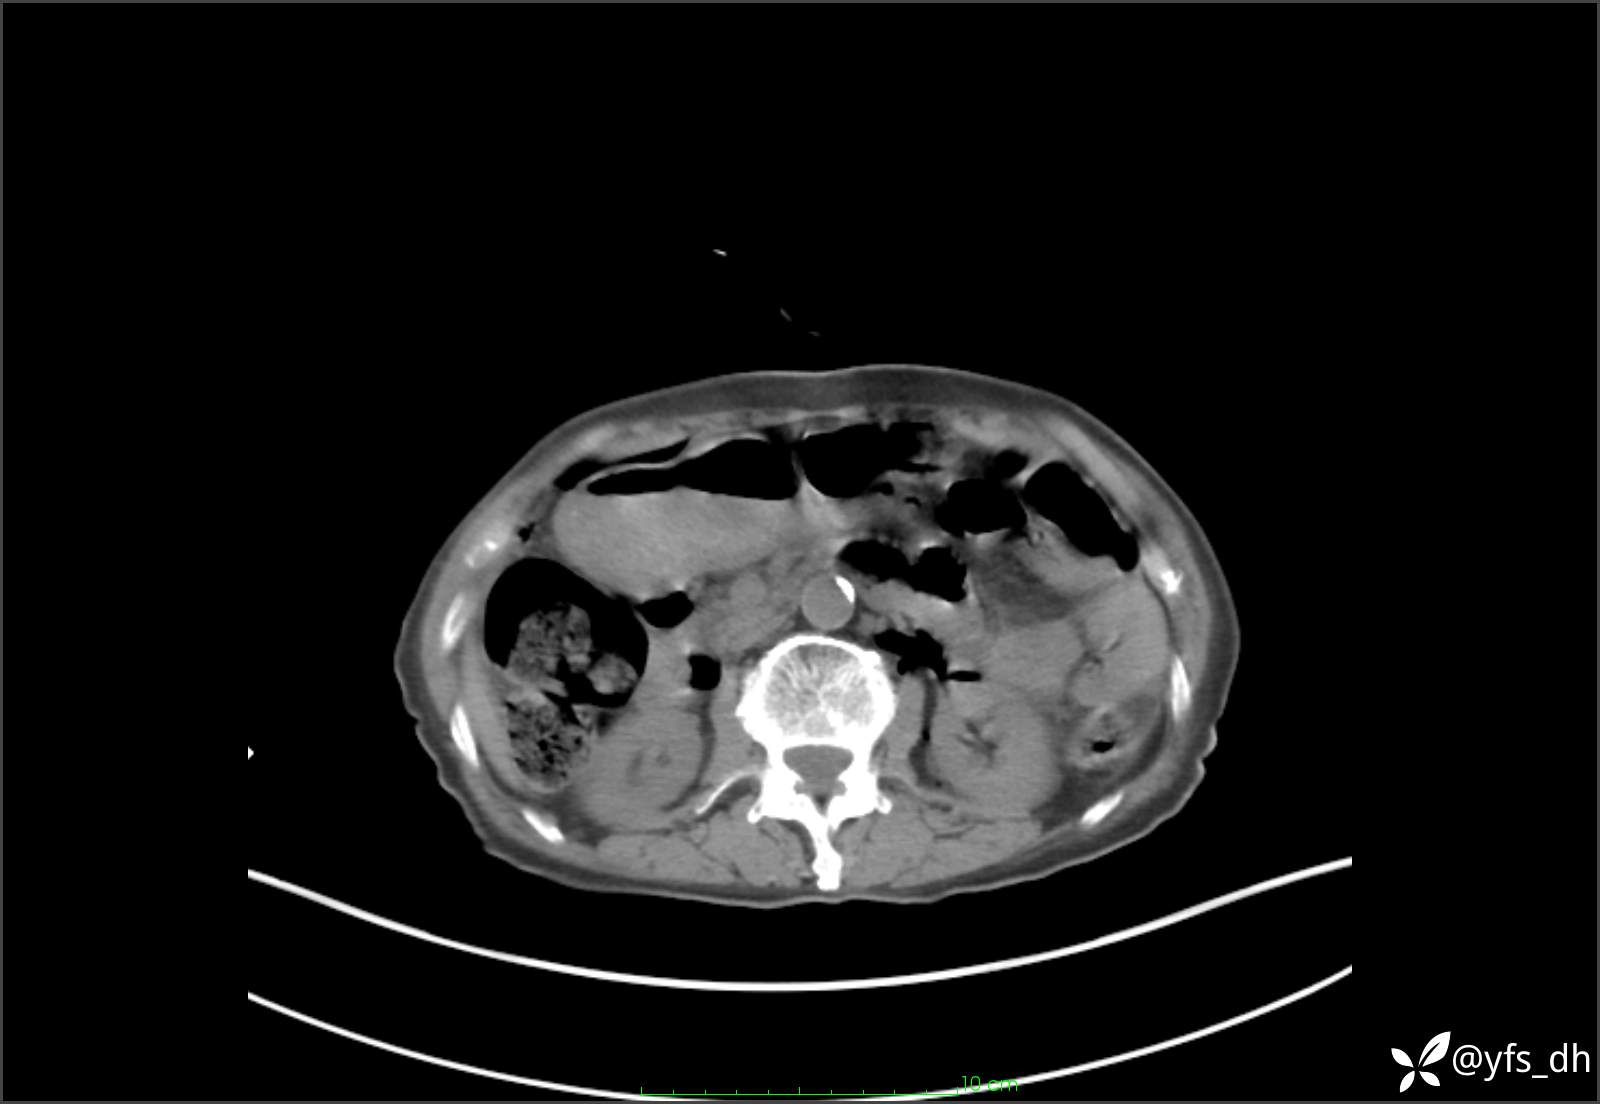

1.简要病史:患者4天前突发上腹部疼痛不适,但可以忍受。3小时前饭后突然加重,不能忍受后就诊。

2.简要手术记录:术中见腹盆腔大量肠液及粪便,乙状结肠中下段见一约3cm的破口。